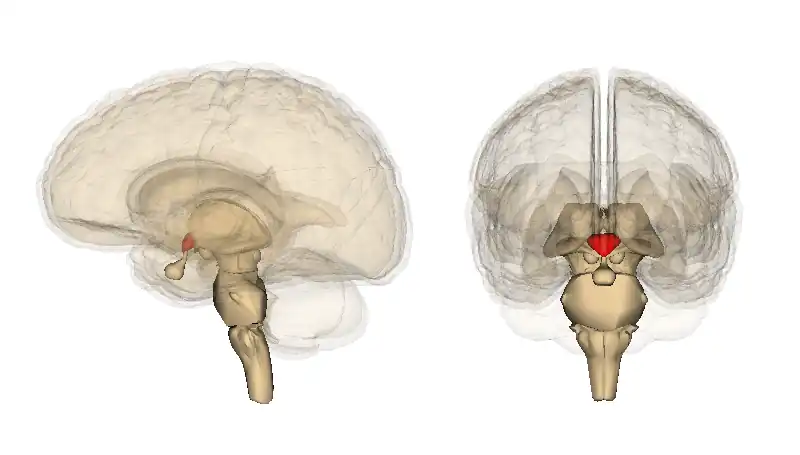

Images from neurological research can create images that show regions in the brain accociated with feelings of sadness. Research can not state the exact cause for emotions, rather areas within the brain activated when emotions arise. There is still debate between the amount of genetic factors and environmental influences which contribute to activating these areas of the brain. It is unexceptional to experience emotion such as sadness, as it is part of human physiology. Hormones play a vital part in emotions. Some primary hormones are, Cortisol, a hormone related to stress, with contributes to poor intellectual functioning, negative affect and low health. Testosterone has a high contribution to sex and arousal, Oxytocin is a hormone which leads people to seek comfort in times of need, bonding tendencies to cope with issues in the world. Dealing with negative feelings requires a release in dopamine. Dopamine enhances functioning. Neuroimaging and neurological studies have found that sad facial expressions enhanced activity in the left amygdala and right temporal pole. Sad expressions activate the amygdala region and lesions’ in this region have demonstrated difficulty in recognising expressions. Emotional expression is learnt through the amygdala (Dolan,1999). Dopamine originator of Norepinephrine,which has resulted from tyrosine which comes from diet, comes from regions in the brain stem, the locus ceruleuis and lateral tegmentum. These regions send axons to the cerbellum, spinal cored and amygdala. This shapes conciousness and emotional response. A shortage in dopamine production can effect norepinephrine production. This results in lethargy and low levels of energy, which results in a struggle to get up and go. An excessive amount of dopamine can lead the psychotic moods (Mendius, 2008). Positron emission tomography (PET) studies of emotion have reflected that areas of the brain which have shown activity for sadness are bilateral inferior and orbitofrontal cortex. bilaterally in anterior cingulate,medial prefrontal, and mesial temporal cortex, as well as in brainstem, thalamus, and caudate/putamen (Lane et al,1997). Ekman and Friesen focussed on facial expressions and the human race being universal and without influence from cultural factors. Studies in this field find that infants exhibit expressions of anger, fear, happiness, sadness, surprise and disgust even in such beginning life (Lane et al,1997). Similar to Ekman and Friesens study with men and facial expression, Lane, Reiman, Ahern, Schwartz,& Davidson (1997), experimented on the brain activity and emotions. Using 12 neurologically and psychiatrically, between 18and 30 who were female participants Positron emission tomography was used to measure regional brain activity. There were 12 conditions for each participant, happiness, sadness, and disgust and three control conditions, each induced by film and recall. Emotion and control tasks were alternated throughout. Condition order was pseudorandomized and counterbalanced between the particpants. For each emotion and control condition the brain regions were examined. Results support that varying brain regions are responsible for various emotion.